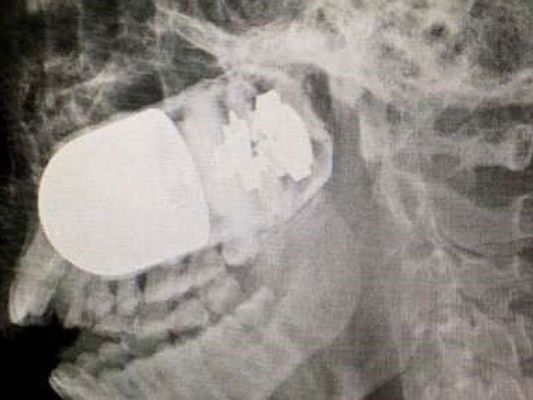

Ärzte operieren Granate aus Kopf eines Soldaten

Das Geschoss drang auf der rechten unteren Seite in den Schädel des Soldaten ein. Weil ein Transport per Hubschrauber zu gefährlich war, wurde der Soldat in einem Krankenwagen ins Militärkrankenhaus in der Hauptstadt Bogota gebracht, wie die Zeitung “El Tiempo” am Donnerstag berichtete. Die Fahrt dauerte acht Stunden. Weil die Granate zu explodieren drohte, bauten die Ärzte auf dem Parkplatz der Klinik einen improvisierten Operationssaal auf.

Schließlich wurde das Geschoss erfolgreich entfernt. “Es waren fünf entscheidende Minuten”, sagte Chef-Chirurg William Sanchez Maldonado. “Wenn die Granate explodiert wäre, hätte es eine Tragödie gegeben.” Der Zustand des Patienten ist seit der Operation am vergangenen Sonntag stabil. Um das Gesicht des Soldaten wieder herzustellen, sind allerdings noch bis zu vier weitere Operationen notwendig.